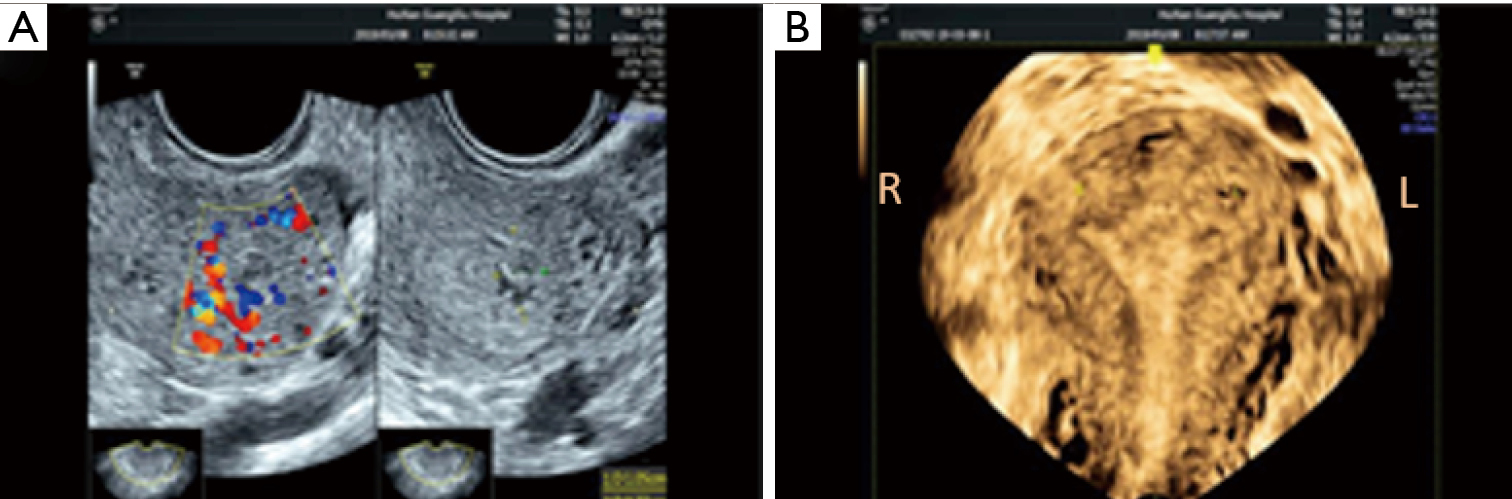

Tiate from retained products of conception RPOC. Retained products of conception POCs can occur after spontaneous or induced abortion and after delivery. This patient had hypervascular retained products of conception RPOC.

Vascular Grading Of Retained Products Of Conception On Ultrasound And Download Scientific Diagram